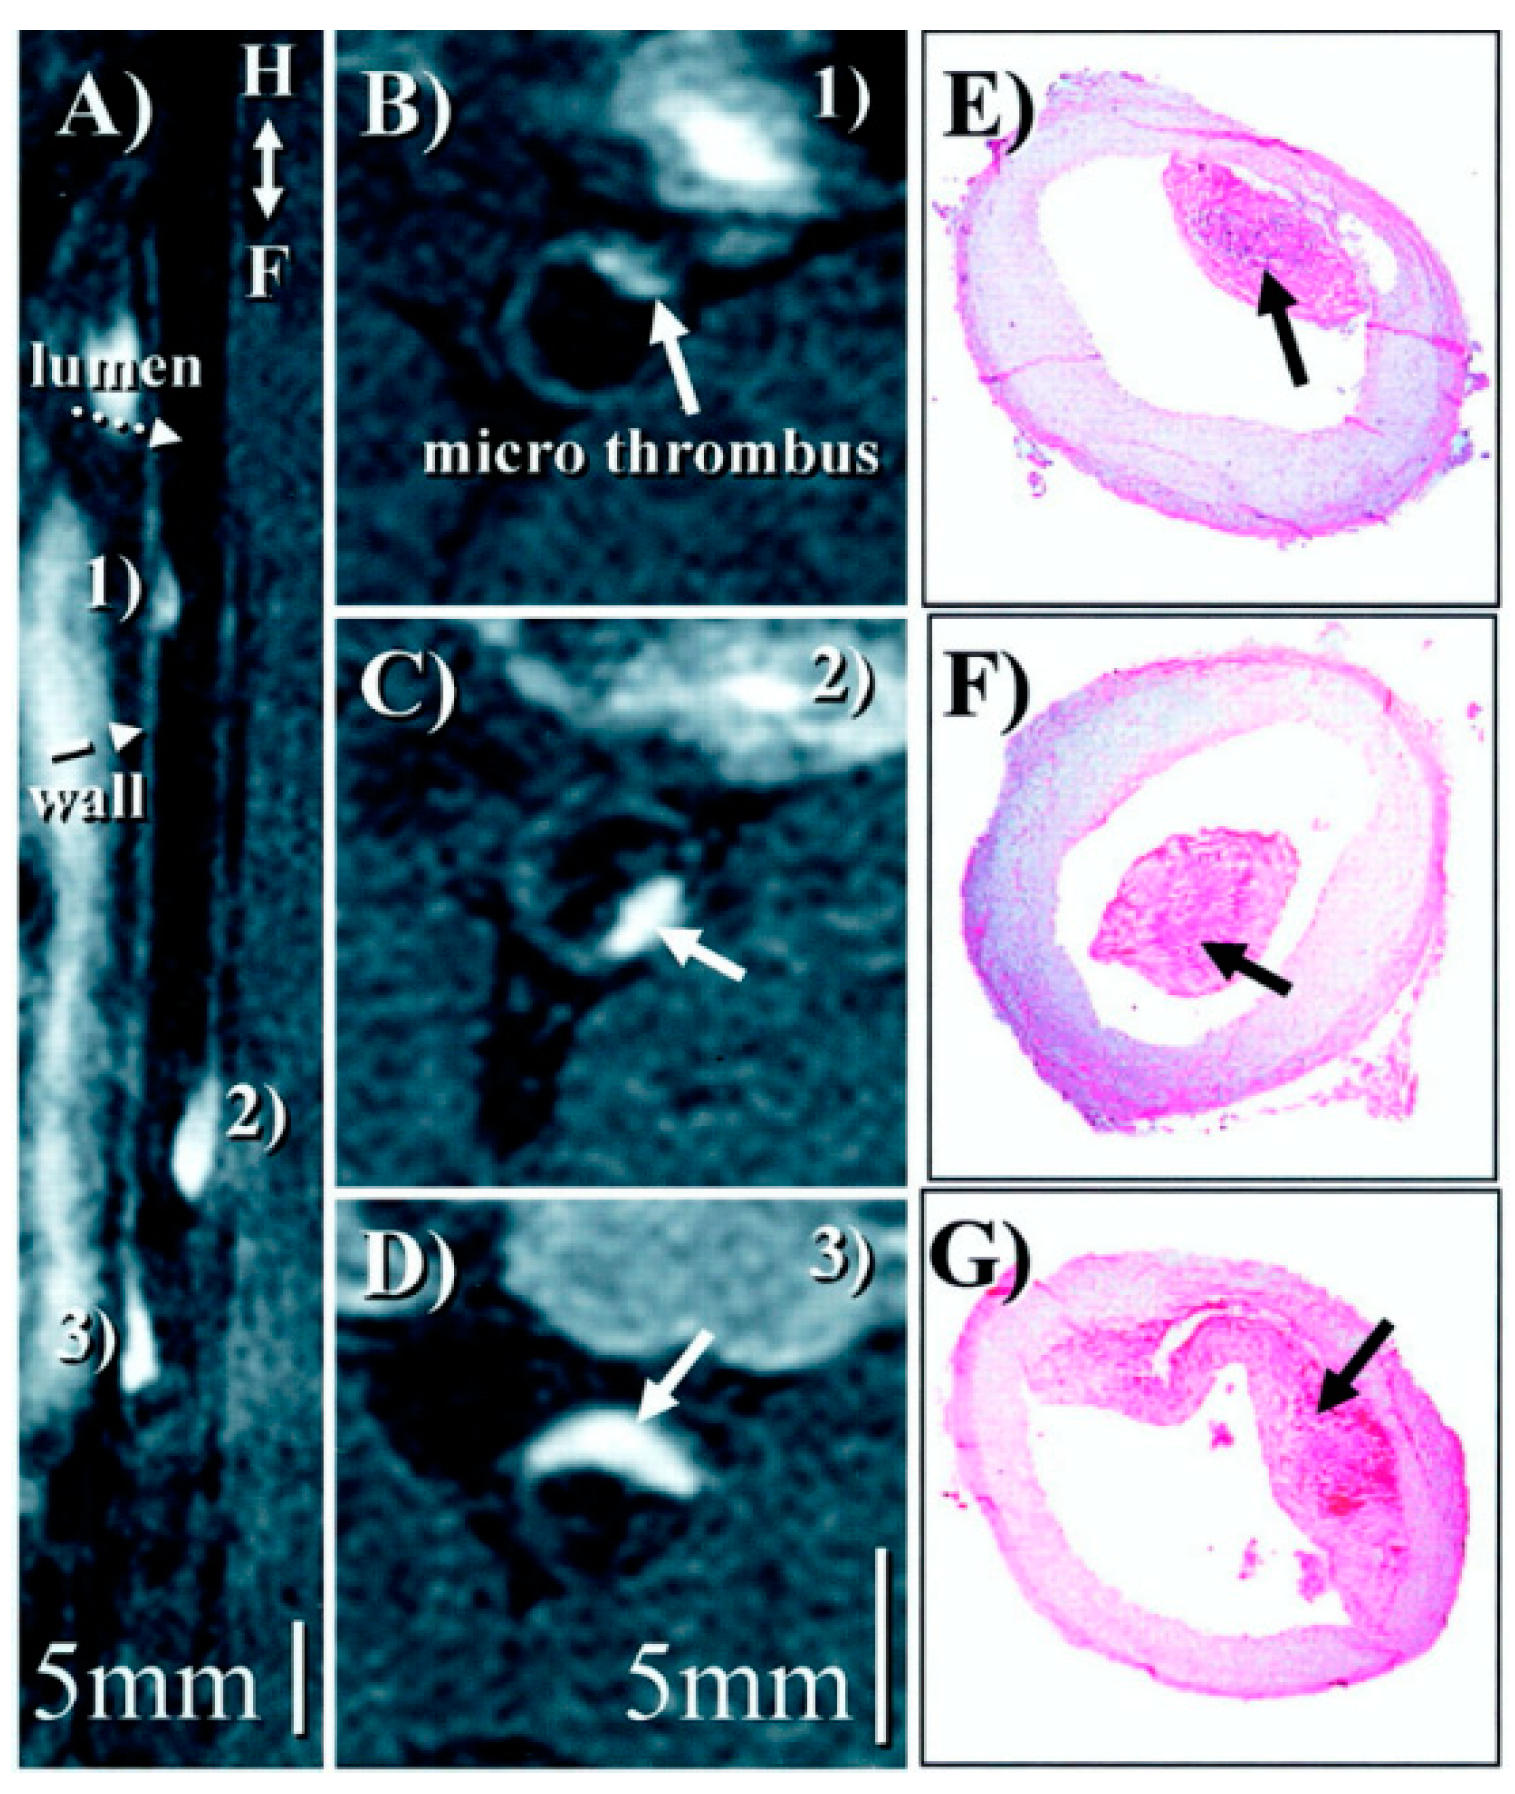

- Andia, M.E.; Saha, P.; Jenkins, J.; Modarai, B.; Wiethoff, A.J.; Phinikaridou, A.; Grover, S.P.; Patel, A.S.; Schaeffter, T.; Smith, A.; et al. Fibrin-Targeted Magnetic Resonance Imaging Allows In Vivo Quantification of Thrombus Fibrin Content and Identifies Thrombi Amenable for Thrombolysis. Arterioscler. Thromb. Vasc. Biol. 2014, 34, 1193–1198. [Google Scholar] [CrossRef]

- Spuentrup, E.; Katoh, M.; Buecker, A.; Fausten, B.; Wiethoff, A.J.; Wildberger, J.E.; Haage, P.; Parsons, E.C.; Botnar, R.M.; Graham, P.B.; et al. Molecular MR Imaging of Human Thrombi in a Swine Model of Pulmonary Embolism Using a Fibrin-Specific Contrast Agent. Investig. Radiol. 2007, 42, 586–595. [Google Scholar] [CrossRef]

- Hara, T.; Bhayana, B.; Thompson, B.; Kessinger, C.W.; Khatri, A.; McCarthy, J.R.; Weissleder, R.; Lin, C.P.; Tearney, G.J.; Jaffer, F.A. Molecular imaging of fibrin deposition in deep vein thrombosis using fibrin-targeted near-infrared fluorescence. JACC Cardiovasc. Imaging 2012, 5, 607–615. [Google Scholar] [CrossRef]

- Blasi, F.; Oliveira, B.L.; Rietz, T.A.; Rotile, N.J.; Naha, P.C.; Cormode, D.P.; Izquierdo-Garcia, D.; Catana, C.; Caravan, P. Multisite Thrombus Imaging and Fibrin Content Estimation With a Single Whole-Body PET Scan in Rats. Arterioscler. Thromb. Vasc. Biol. 2015, 35, 2114–2121. [Google Scholar] [CrossRef]